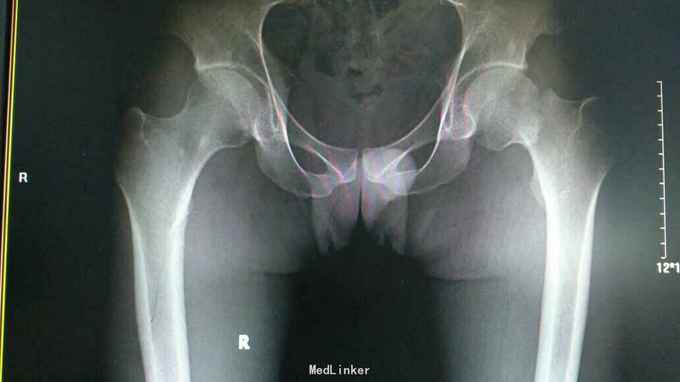

24岁男性,运动中摔倒致左髋疼痛活动受限,

左髋部压痛,大粗隆扣痛,下肢杆力消失,x光及CT证实左股骨颈骨折